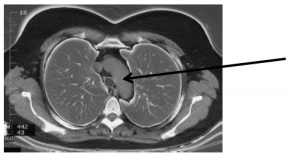

Qual é o ponto assinalado pela seta na

imagem de tomografia a seguir?